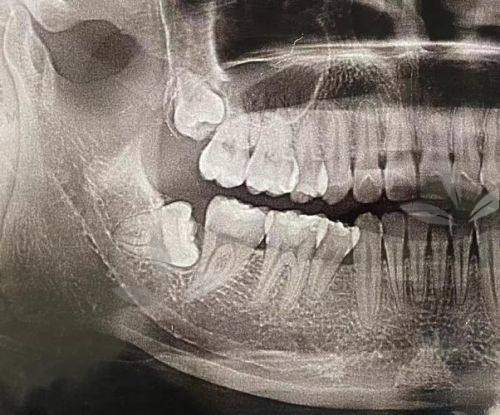

特别多人第一次拔牙完成后的第一反应可能是:“震惊!拔完牙后牙槽骨会重新长出来吗?”这个问题不仅困扰着正在接受拔牙治疗的人,更承载着特别多人对口腔修复机制的好奇。要知道一颗牙齿的缺失,不仅是“咬不动”的烦恼,更牵扯到整个面部结构稳定以及未来是否能顺利种牙。所以今天我们就来好好说说——牙齿拔掉之后,空出的牙槽骨,到底能不能像传说那样“再生”?

先来个小科普:牙槽骨是啥?它就是你牙齿底下的“地基”,把牙固定在口腔内。拔完牙齿之后,这个地基由于“上层建筑”没了,会发生结构上的调整。

短时间内,牙槽骨会开始吸收,也就是说它会慢慢变窄、变低一些,这是自然反应。不过别慌,这并不意味着你“毁容”了,只要处理得当,它也能自我修复。

拔牙后的牙槽骨确实具备“神奇的再生能力”,它并不会因为牙齿不见了就完全“罢工”。相反,它会启动一个叫“骨改建”的自修过程,通过吸收老骨、生成新骨来逐渐填补拔牙留下的空间。

这个过程听起来高大上,其实就像“翻新装潢”差不多。但再生不是瞬间魔法,需要时间、条件加护理三大核心因素一起发力。

牙槽骨不是“种子发芽”一夜搞定,一般拔牙后,2-3个月是初步愈合期,想着种牙的大概需要3-6个月的完整骨愈合期。但如果采用植骨方式(比如用骨粉填补),那就另当别论,可以加快速度甚至改善骨量条件。

• CBCT三维影像:目前比较常用的方式,可以立体显示牙槽骨厚度、高度和密度情况。